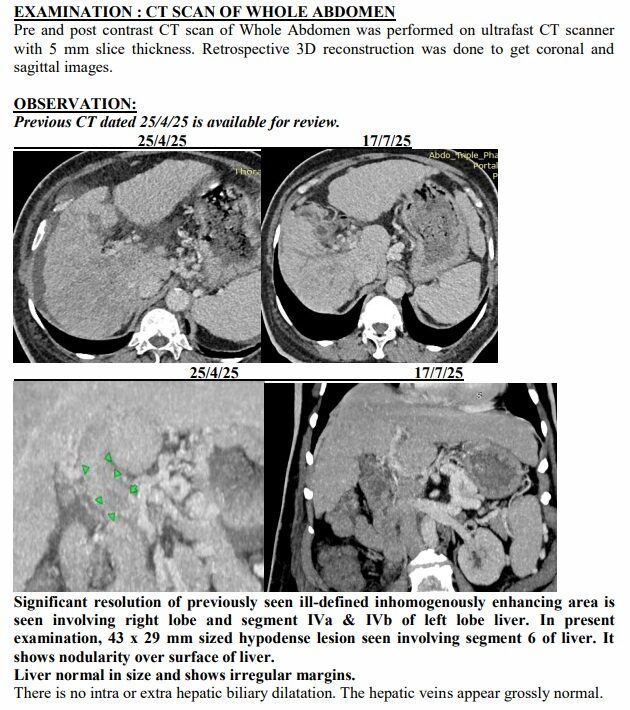

Surat (Gujarat) [India], August 22: On a hot April afternoon in Surat, the Patel family sat in a crowded hospital waiting room, clutching a CT scan report that felt heavier than paper. The words were sharp, merciless: advanced liver cancer, spread across both lobes, blocked veins, fluid buildup, bone changes. For 74-year-old Ravjibhai (name changed), the doctors spoke plainly: there was no cure left, only comfort care.

Yet just three months later, on another afternoon in July, the same family stared at a different scan. The tumours had shrunk to one patch. Blood was flowing again. The swelling was gone. Even the alarming tumour marker that had shot up to 1,000 ng/mL had fallen to 10, back in the safe zone. For a man who had been fading fast, it was a turnaround no one in the room dared to predict.

The July scan sealed what they were already feeling at home. The many shadows in his liver had shrunk into one. His abdomen, once swollen with fluid, was flat again. His numbers, which had scared even seasoned oncologists, were suddenly within range.

A senior radiologist who reviewed both reports told this correspondent, “Such a reversal in advanced liver cancer is extremely rare. Clinically, it borders on the unbelievable.”